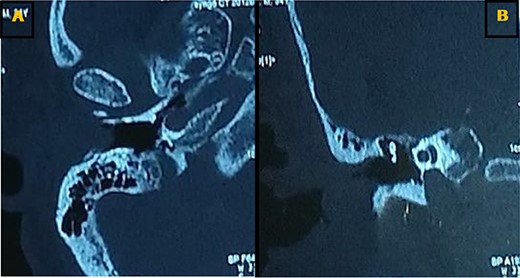

Our patient was a 40-year-old female, with unremarkable disease history, who presented with a fullness of the right ear for 6 months which was associated with progressive hypoacusis and intermittent ipsilateral tinnitus. The clinical examination showed a mass in the right external auditory canal, attached to the posterosuperior wall, which was smooth, pink, firm, mobile, well limited and hemorrhagic on contact (Fig. 1). Weber and Rinne tuning fork tests were negative and right-lateralized, respectively. Preoperative pure tone audiometry revealed an average right conductive hearing loss of 37.5 dB. Imaging based on computed tomography (CT) scan showed a mass occupying the outer two-thirds of the right external auditory canal, measuring 17 mm, well limited, with regular contours. The tissue radio density measured was 61 HU with erosion of the middle ear (Fig. 2).

Axial (A) and coronal (B) CT scans showing a tissue lesion process of the external auditory canal with erosion of the eardrum and filling of a few mastoid cells.